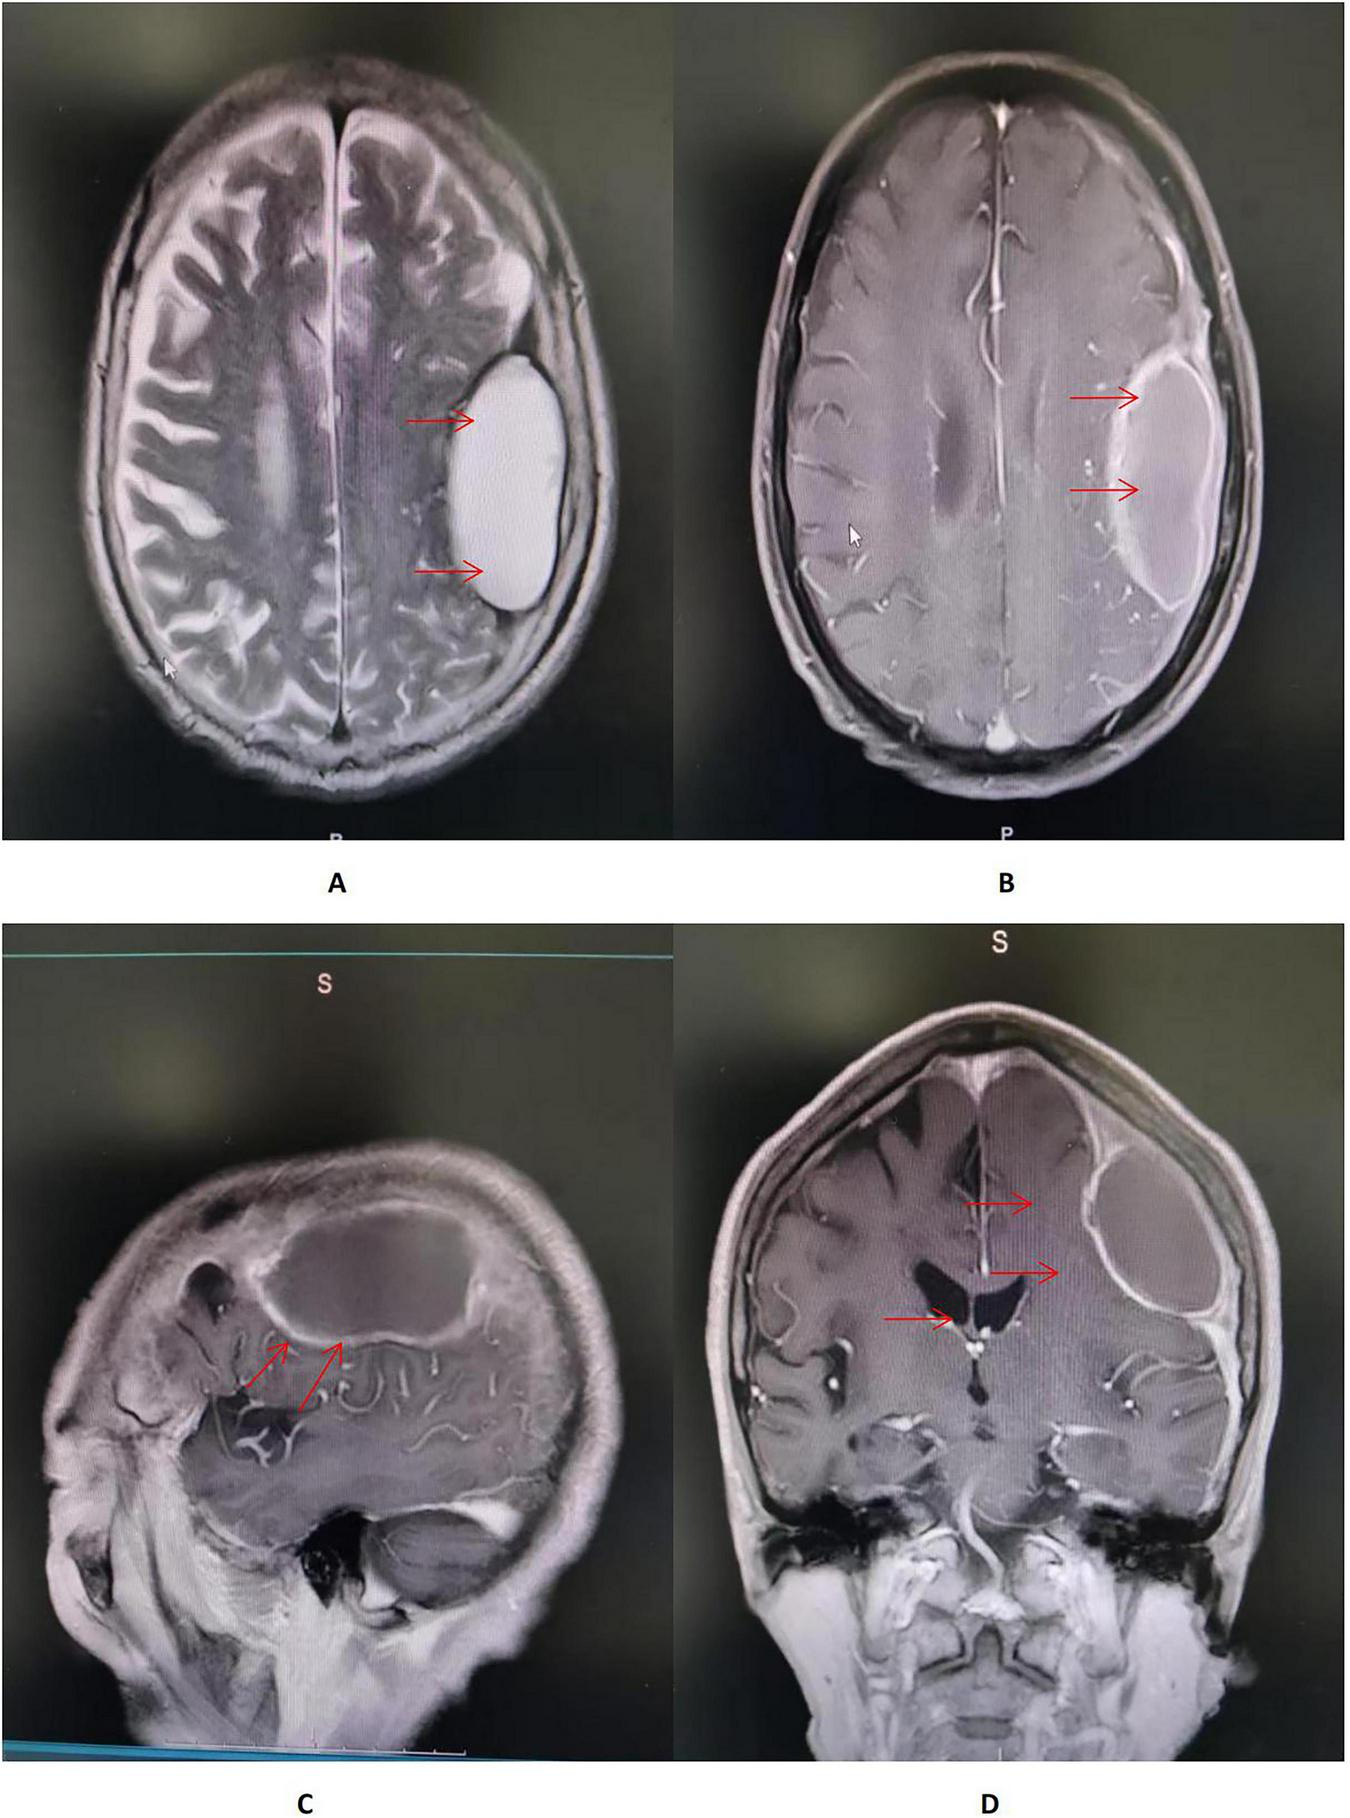

On hospital day 7, axial T2-weighted/FLAIR and T1-weighted MRI of the head demonstrate a mass-like abnormal signal focus in the left frontoparietal region, measuring approximately 31 mm × 58 mm. The lesion appeared hyperintense on T2-weighted/FLAIR images and iso- to hypointense on T1-weighted images. A significant perilesional edema was present in coronal contrast-enhanced T1-weighted MRI, causing mild mass effect and displacement of the surrounding brain structures (Figure 2). Spinal MRI showed no abnormal signal intensity suggestive of involvement (Figure 3). Lumbar puncture was immediately performed. Opening pressure was elevated at 220 mmH2O, and the CSF appeared turbid. Routine CSF analysis (Table 1) demonstrated: white blood cell (WBC) count 460/mm3, Pandy’s test positive, total protein 1312 mg/L, glucose 0.99 mmol/L, chloride 115.9 mmol/L, and a standard tube agglutination test (SAT) titer of 1:480. Metagenomic next-generation sequencing (mNGS) of the CSF detected 3489 sequence reads of Brucella melitensis. The diagnosis was revised to neurobrucellosis (meningitis) complicated by giant intracranial abscess formation. Simultaneously, we cultured the cerebrospinal fluid on Columbia blood agar plates at an ambient temperature of 35 degrees Celsius. Following the current Chinese guidelines for neurobrucellosis (10), antimicrobial therapy was intensified with the addition of ceftriaxone (2 g every 12 h). Mannitol (125 mL every 8 h) was initiated for intracranial pressure reduction, and dexamethasone (10 mg once daily) was added to mitigate inflammatory exudation. Subsequently, the patient’s headaches began to subside.

FIGURE 2

(A,B) Axial T2-weighted/FLAIR and T1-weighted MRI of the head demonstrate a mass-like abnormal signal focus (red arrow) in the left frontoparietal region, measuring approximately 31 × 58 mm. The lesion appeared hyperintense on T2-weighted/FLAIR images and iso- to hypointense on T1-weighted images, situated immediately beneath the inner table of the skull. A moderate perilesional edema was observed, with localized effacement of adjacent sulci. No significant midline shift was identified. (C) Sagittal contrast-enhanced T1-weighted MRI of the head showed an in homogeneously enhancing lesion in the left frontoparietal region, abutting the dura mater with a prominent “dural tail sign” (red arrow). The lesion had well-defined margins, and the surrounding edema showed no enhancement. (D) Coronal contrast-enhanced T1-weighted MRI of the head demonstrated a large mass lesion with rim enhancement and a non-enhancing central area, suggestive of cystic or necrotic components. A significant perilesional edema was present, causing mild mass effect and displacement of the surrounding brain structures (red arrow).